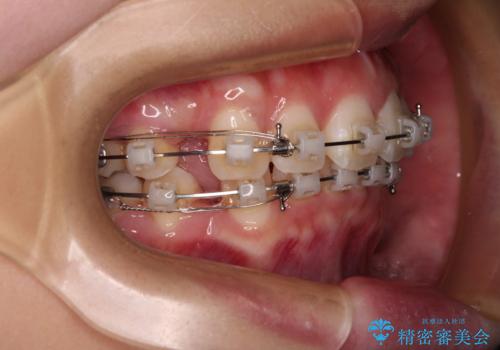

- 矯正装置

- クリアブラケット

- 前歯部のデコボコと口元が出ているのが気になるとのことで来院された患者様です。

口元の突出感の解消と、このままデコボコを解消するとさらに出っ歯傾向になってしまうことを考慮し、上下左右の小臼歯を抜歯しクリアブラケットにて矯正していくこととしました。